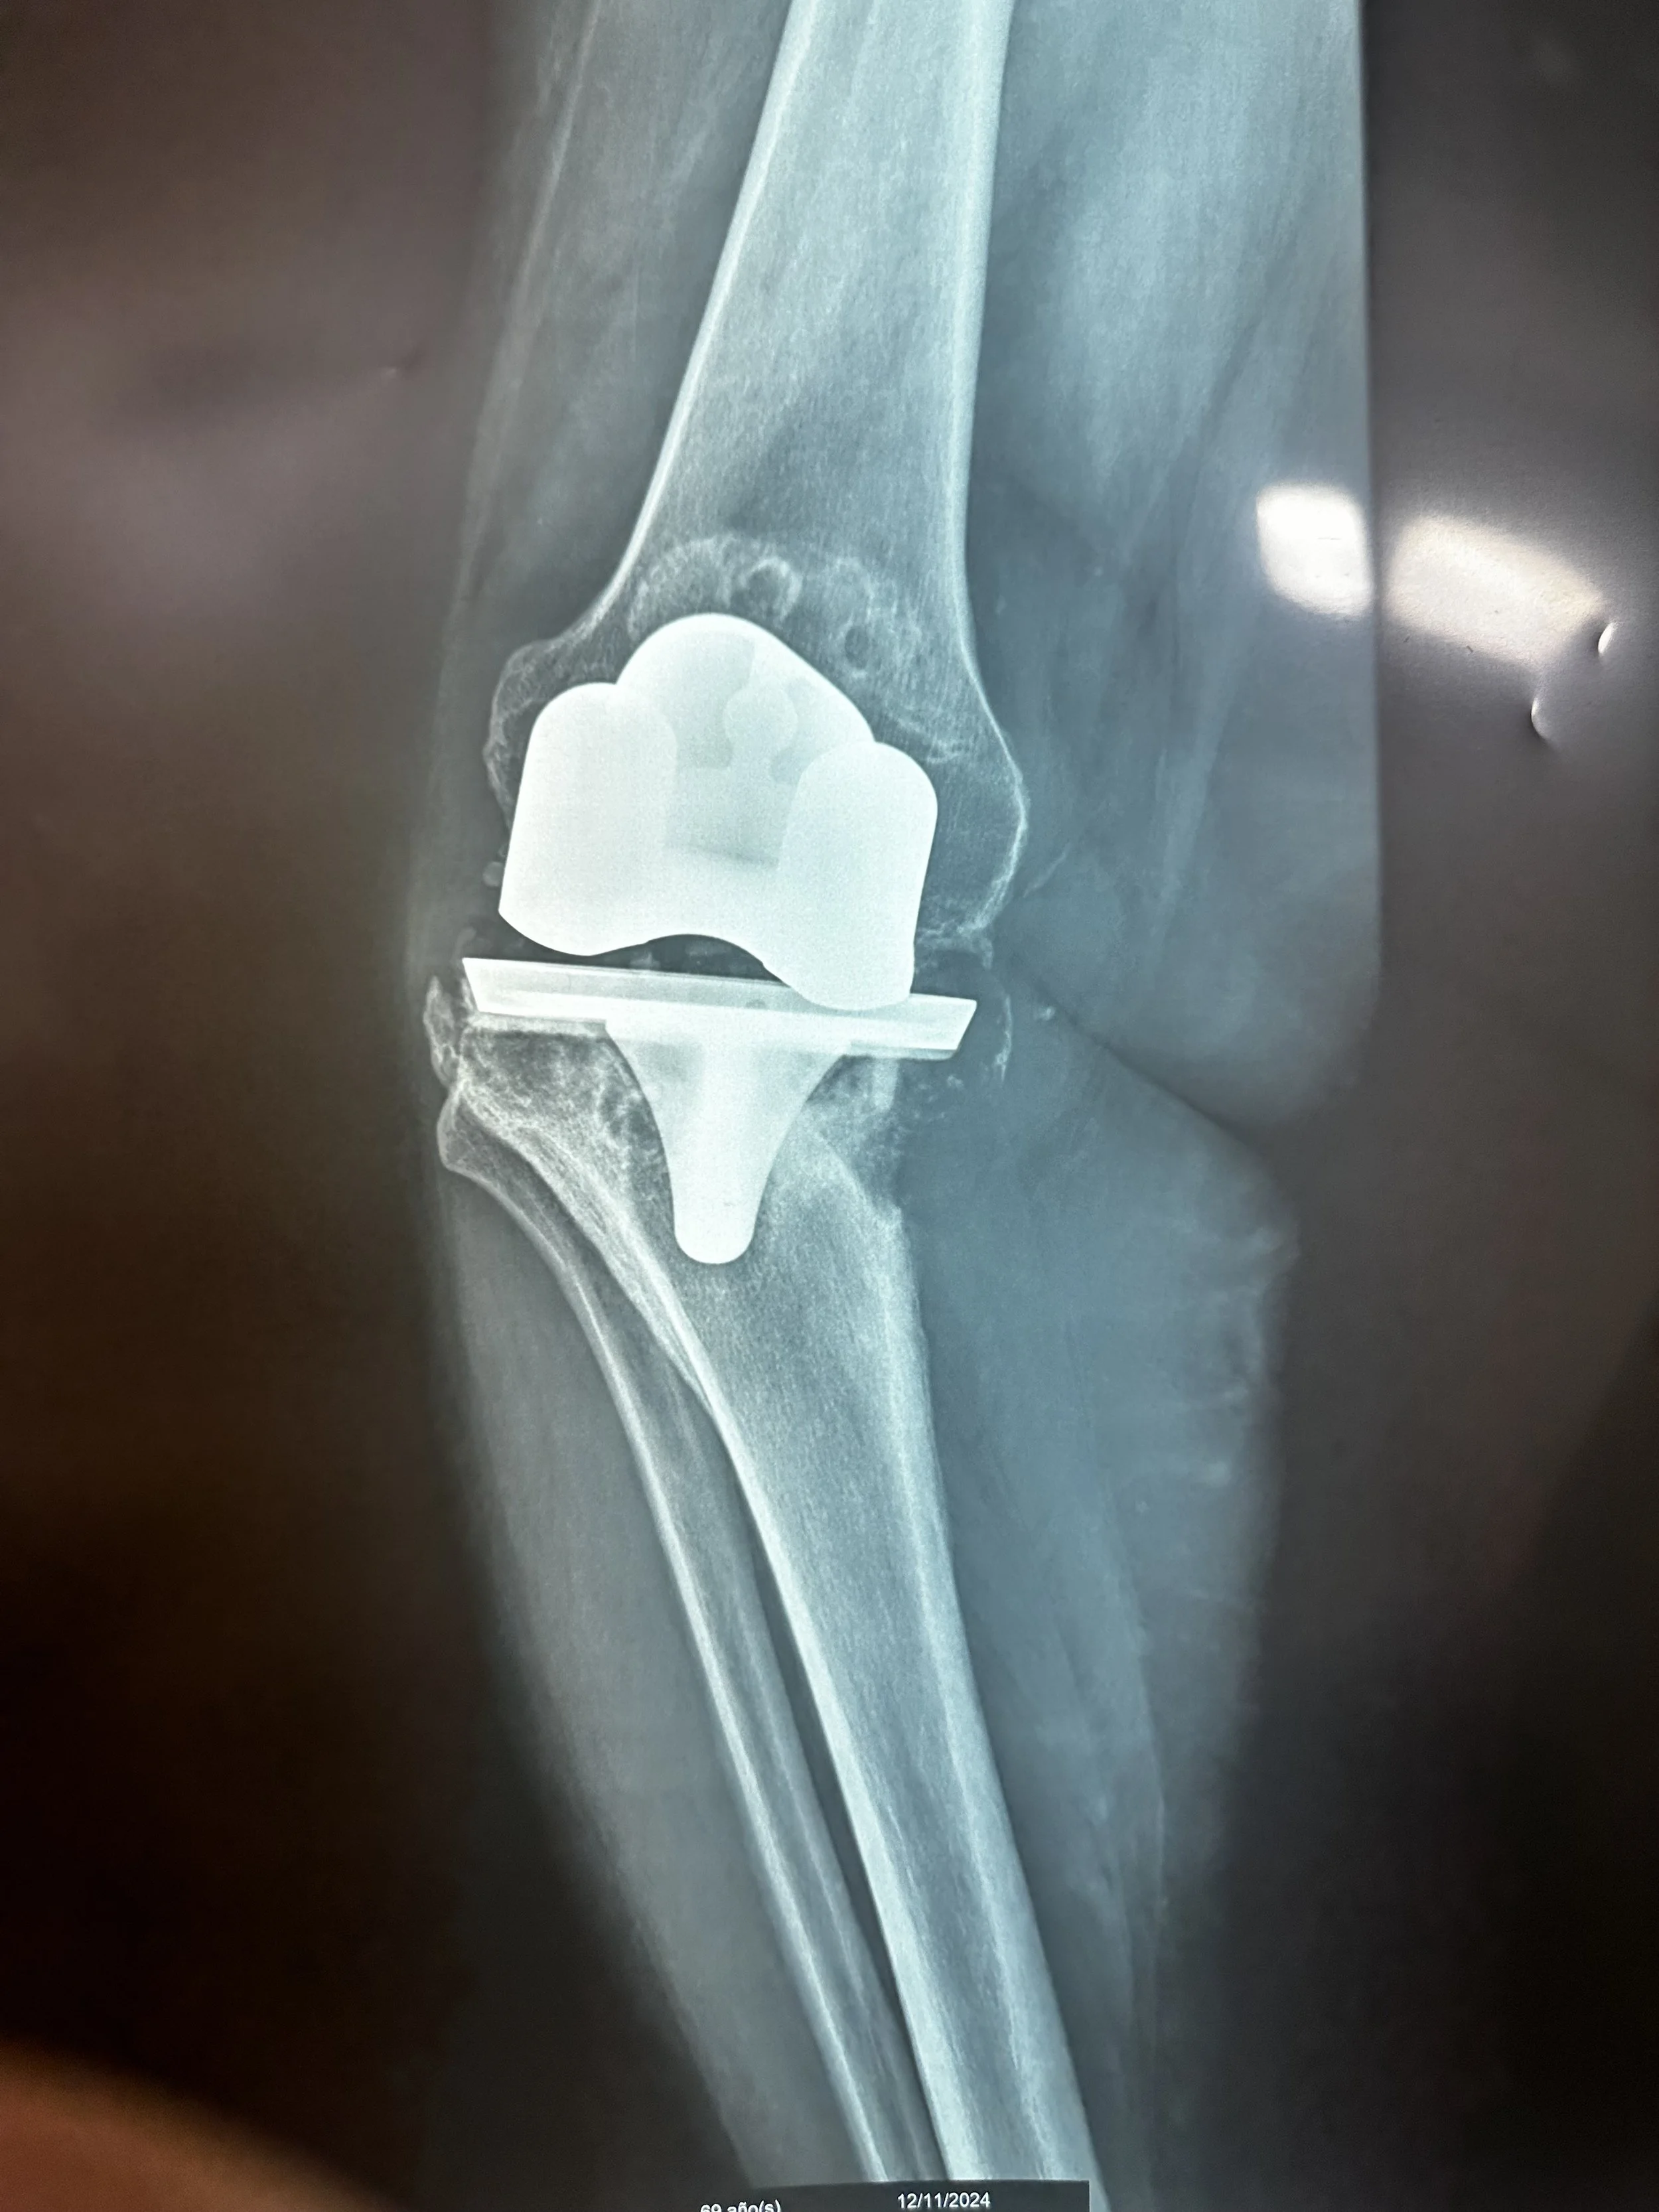

Once back at the hospital, everyone jumped into their positions, with five operating rooms running simultaneously. By the end of the day, the team had performed 24 procedures, including 7 total hips, 13 total knees, and 4 foot & ankle. From a warm word of assurance and prayer during pre-op to the professional teamwork in surgery to the gentle hand guiding in recovery, every Team HIM member performed their responsibilities with passion, joy, and diligence.